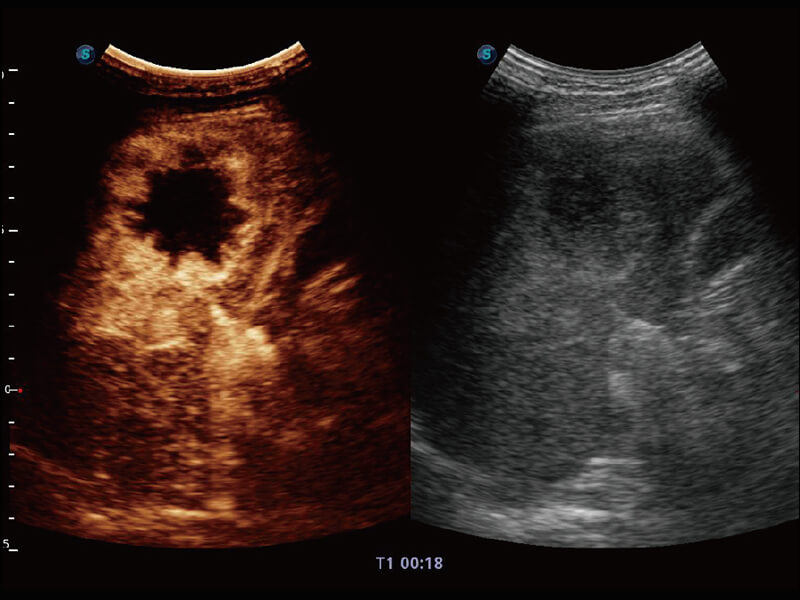

Micro F 显微血流成像 明察秋毫